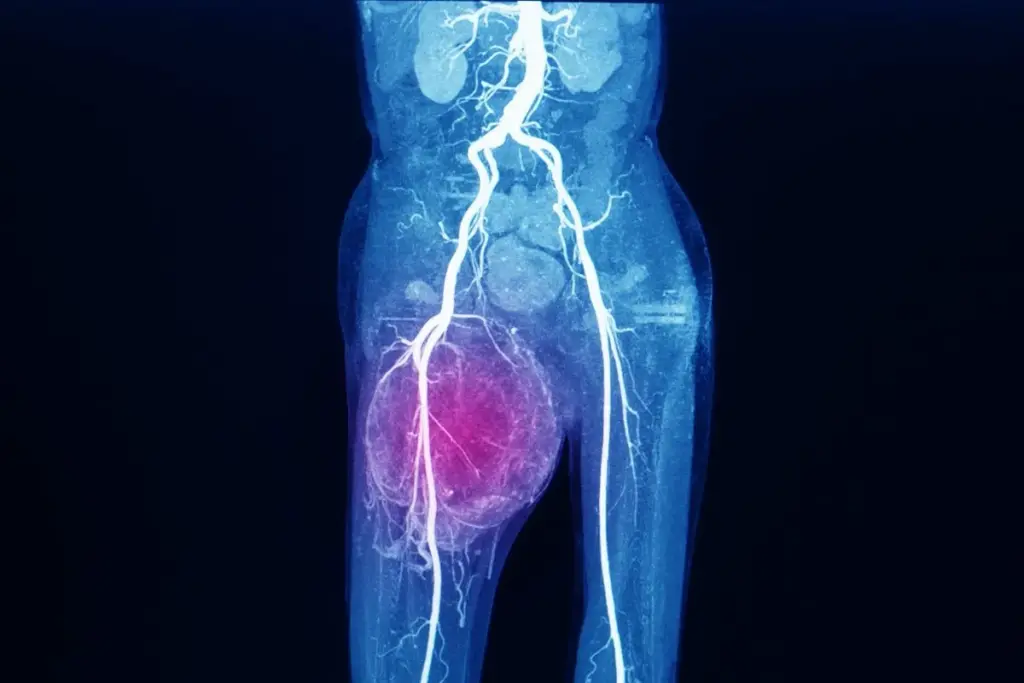

1. Imaging: MRI is the preferred modality for soft‑tissue assessment, while CT scans provide detailed bone evaluation. PET‑CT can detect metastatic spread.

2. Biopsy: Core‑needle or incisional biopsy yields tissue for microscopic examination. Image‑guided techniques ensure precise sampling.